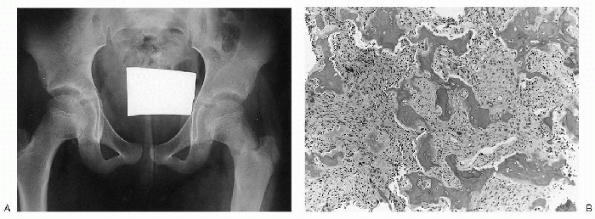

Figure 23-12 Fibrous dysplasia. (A)

Anteroposterior radiograph of the pelvis shows subtle ground-glass density of the left femoral neck and proximal diaphysis. The cortex blends imperceptibly with the medullary canal. A pathologic fracture is seen at the base of the femoral neck. (B) Photomicrograph of the lesion demonstrates irregular woven bone trabeculae (so-called Chinese letters) in a background of bland fibroblastic stroma. Note absence of osteoblastic rimming. |

-

Histologically, fibrous dysplasia (both

(see Fig. 23-12B). -

The osteoid and bone appear to arise in a haphazard fashion from the fibrous stroma.

The trabeculae often obtain a variety of shapes (C’s and O’s) and are sometimes referred to as alphabet soup or Chinese letters.